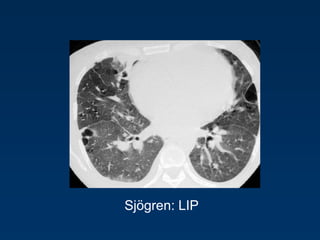

Benign lymphoproliferative disorder

Diffuse interstitial infiltration of

mononuclear cells

Not limited to the air ways as

in follicular Bronchiolitis

LIP

= Lymphocytic Interstitial Pneumonia

Sjögren: LIP

Rarely idiopathic

In association with:

Sjögren’s syndrome

Immune deficiency syndromes, AIDS

Primary biliary cirrhosis

Multicentric Castlemean’s disease

Sjoegren disease

Dry eye and dry mouth

Fibrosis, bronchitis and bronchiolitis

Overlap

Sarcoid, DM/PM, MXCT

SLE, RA (pleural effusion)

Up to 40 x increased risk for lymphoma (mediastinal

adenopathy) and

2 x times increased risk for neoplasma